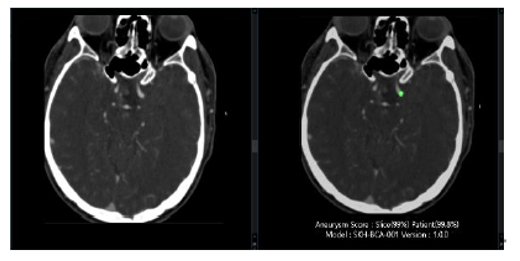

Detects and localizes unruptured cerebral aneurysms using deep learning. Marks aneurysm locations, outlines, and diameter ranges on CTA images.

Download BrochureAI-powered diagnostic support for early, accurate detection and localization of unruptured intracranial aneurysms on CTA, with precise identification of size and shape, including lesions smaller than 3 mm.